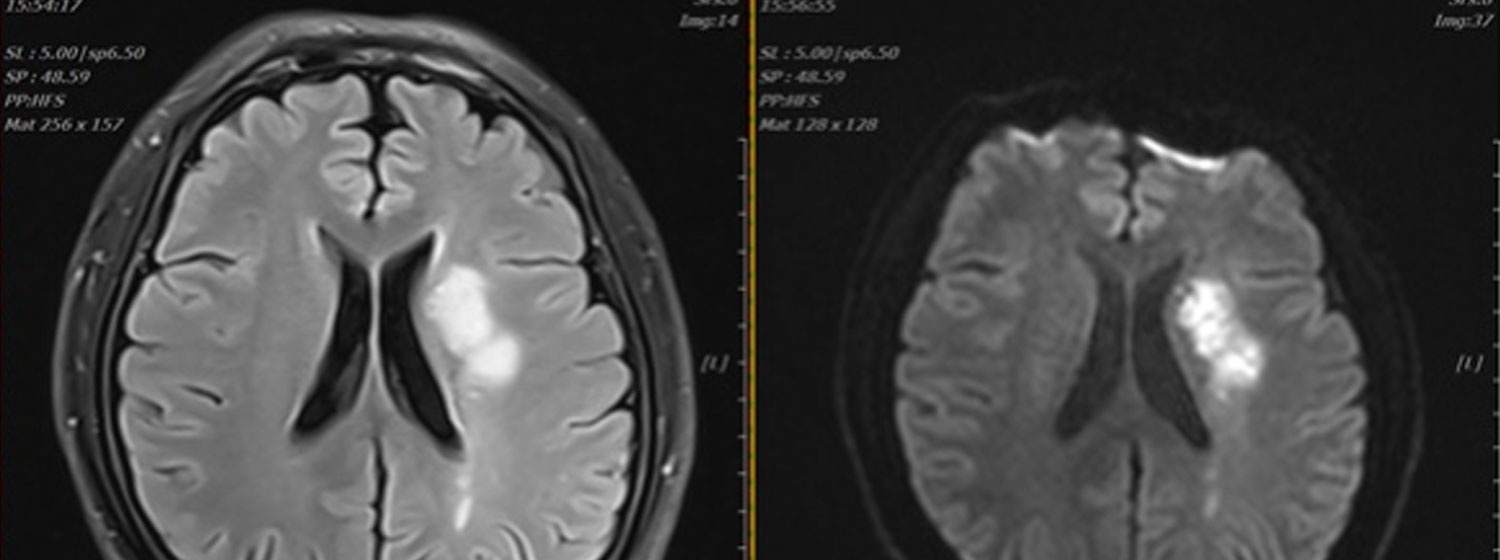

9月2日的凌晨,一场变故悄然袭击了仍忙碌在工作岗位上的吴先生……